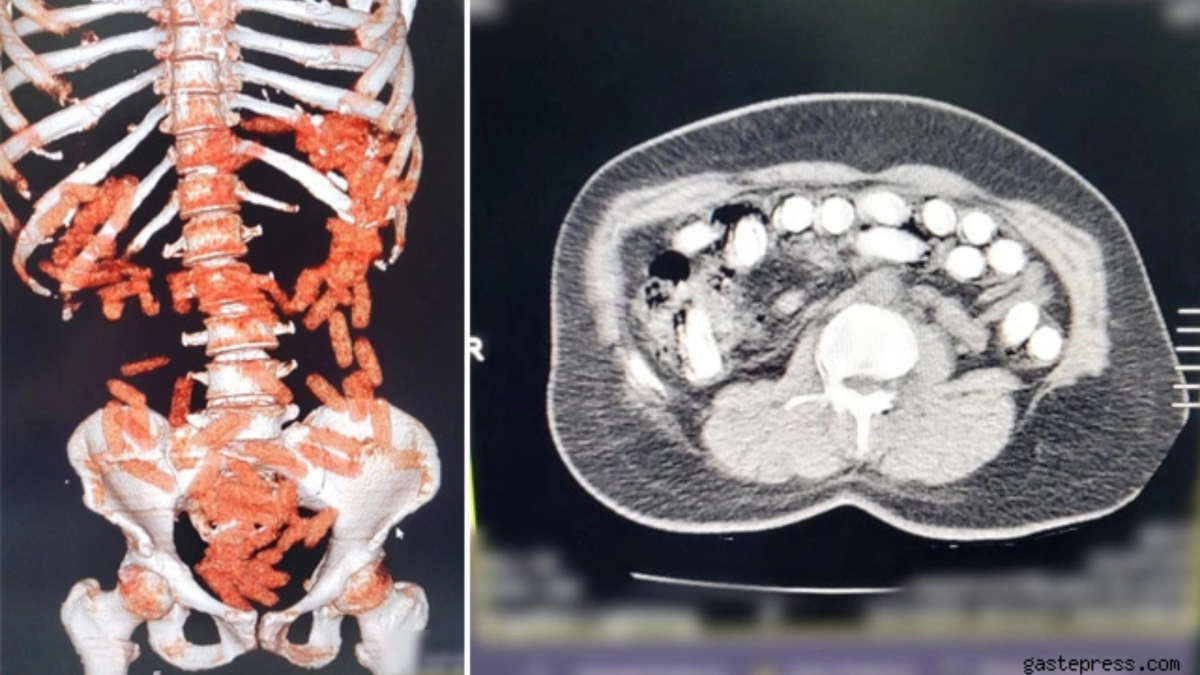

Kayseri’de polis ekipleri tarafından yapılan çalışmalarda yakalanan 2 kişiden birinin midesinden ve bağırsağından 88 kapsül halinde 974 gram uyuşturucu madde ele geçirildi.

Kayseri İl Emniyet Müdürlüğü Narkotik Suçlarla Mücadele Şube Müdürlüğü ekipleri tarafından uyuşturucu madde ticareti yaptığı değerlendirilen şahıslarla ilgili yapılan çalışmalar neticesinde yakalanan A.G.’nin (36) iç beden muayenesinde mide ve bağırsak bölümünde 88 kapsül halinde toplam 974.52 gram uyuşturucu madde tespit edildi. Öte yandan, A.A.’nın (34) yapılan üst aramasında; 2,7 gram uyuşturucu ve 76 adet narkotik hap ele geçirildi.